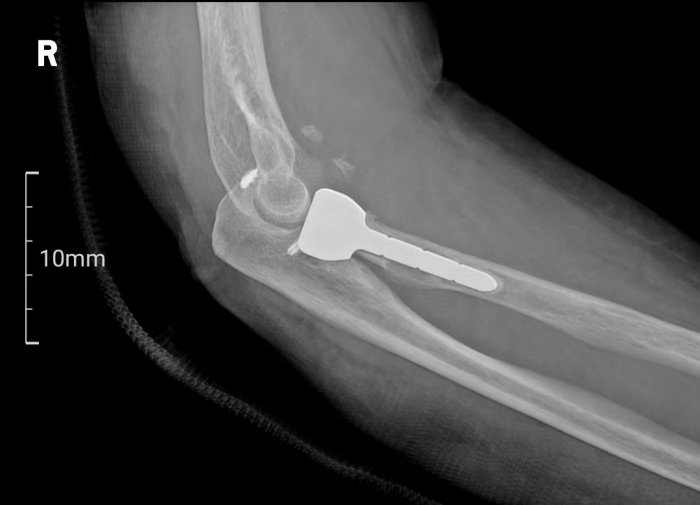

术前二维影像

患者梁女士因不慎跌倒导致右肘关节疼痛并活动受限,经X线检查确诊为肘关节恐怖三联征。面对这一复杂病情,张立主任迅速组织科室医生及3D打印中心技术人员进行病例讨论,并决定采用3D打印桡骨小头置换术进行治疗。

术前,南溪山医院3D打印中心利用高精度扫描技术获取患者肘关节的三维数据,并进行参数化分析,为患者量身定制了3D打印桡骨小头假体。这一假体不仅与患者骨骼高度匹配,还能在手术中即插即用,极大地缩短了手术时间,并确保了手术的精准性和安全性。

手术由张立主任及贵鹏医师团队共同完成。术中,医生们通过5厘米的切口暴露骨折部位,并依据术前规划精准处理骨折断端。随后,3D打印桡骨小头假体被顺利植入,实现了对桡骨头关节面的完美重建。术后,患者恢复顺利,基本功能得到有效恢复。